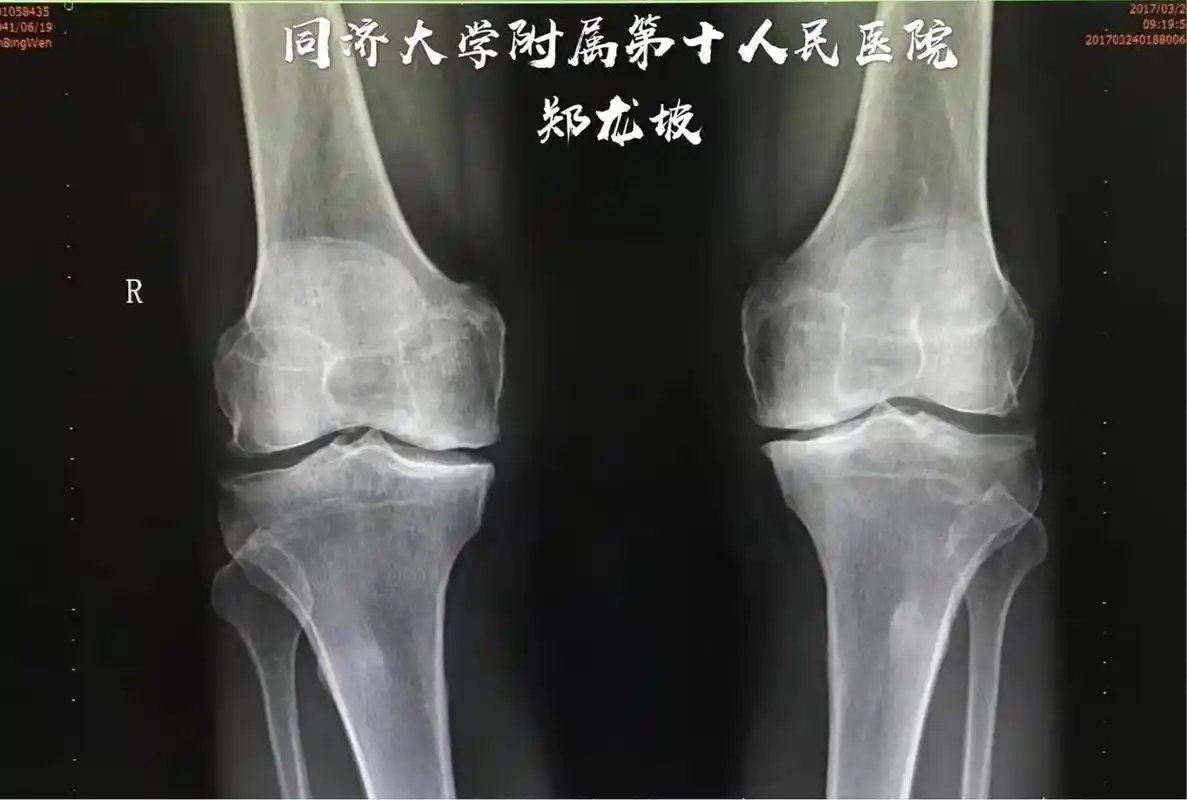

髌骨骨折病人的x光片